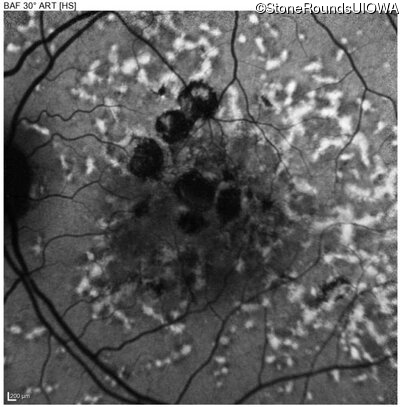

Age at visit: 49 years

This 49 year old man was first told he had a fundus abnormality on a routine eye exam at age 34. Ten years later he noticed some distortion just superior to fixation.

Pattern Dystrophy PRPH2 Gln239Stop CAG>TAG   AD